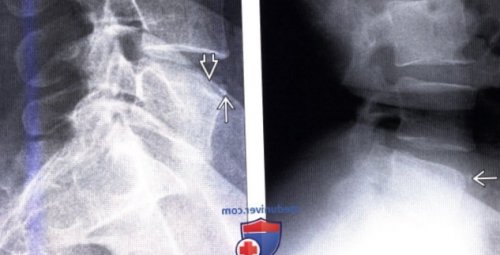

форме дефекта передне-верхнего края L5

проекции: небольшой кортикальный фрагмент, форма которого соответствует

у L3 позвонка. Треугольной формы фрагмент

области передне-верхнего угла какого-либо одного позвонка. В области нижнего

передне-верхнего края L4

края L5 позвонка.

боковой проекции: типичный достаточно крупный тела позвонка, практически соответствующий размерам

(Слева) Рентгенограмма позвоночника в